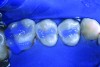

There are now a number of caries detection devices on the market that practitioners can use as an additional tool in finding and diagnosing caries. The DIAGNOdent (KaVo Dental, www.kavousa.com) uses a 655 nm laser to detect fluorescence in tooth decay; both the Spectra Caries Detection Aid (Air Techniques, www.airtechniques.com) (Figure 1) and the Midwest Caries I.D. (DENTSPLY Professional, www.dentsply.com) use a light-emitting diode directed to the occlusal surfaces to determine demineralization and caries. These and other scientific advances benefit clinicians because, although studies have shown that sealing incipient decay will arrest it, frank occlusal decay should not be sealed, nor should primary teeth that are close to exfoliation.

Fig 1. The Spectra is one of the available tools for caries detection. (Courtesy of Air Techniques.)

Figure 1